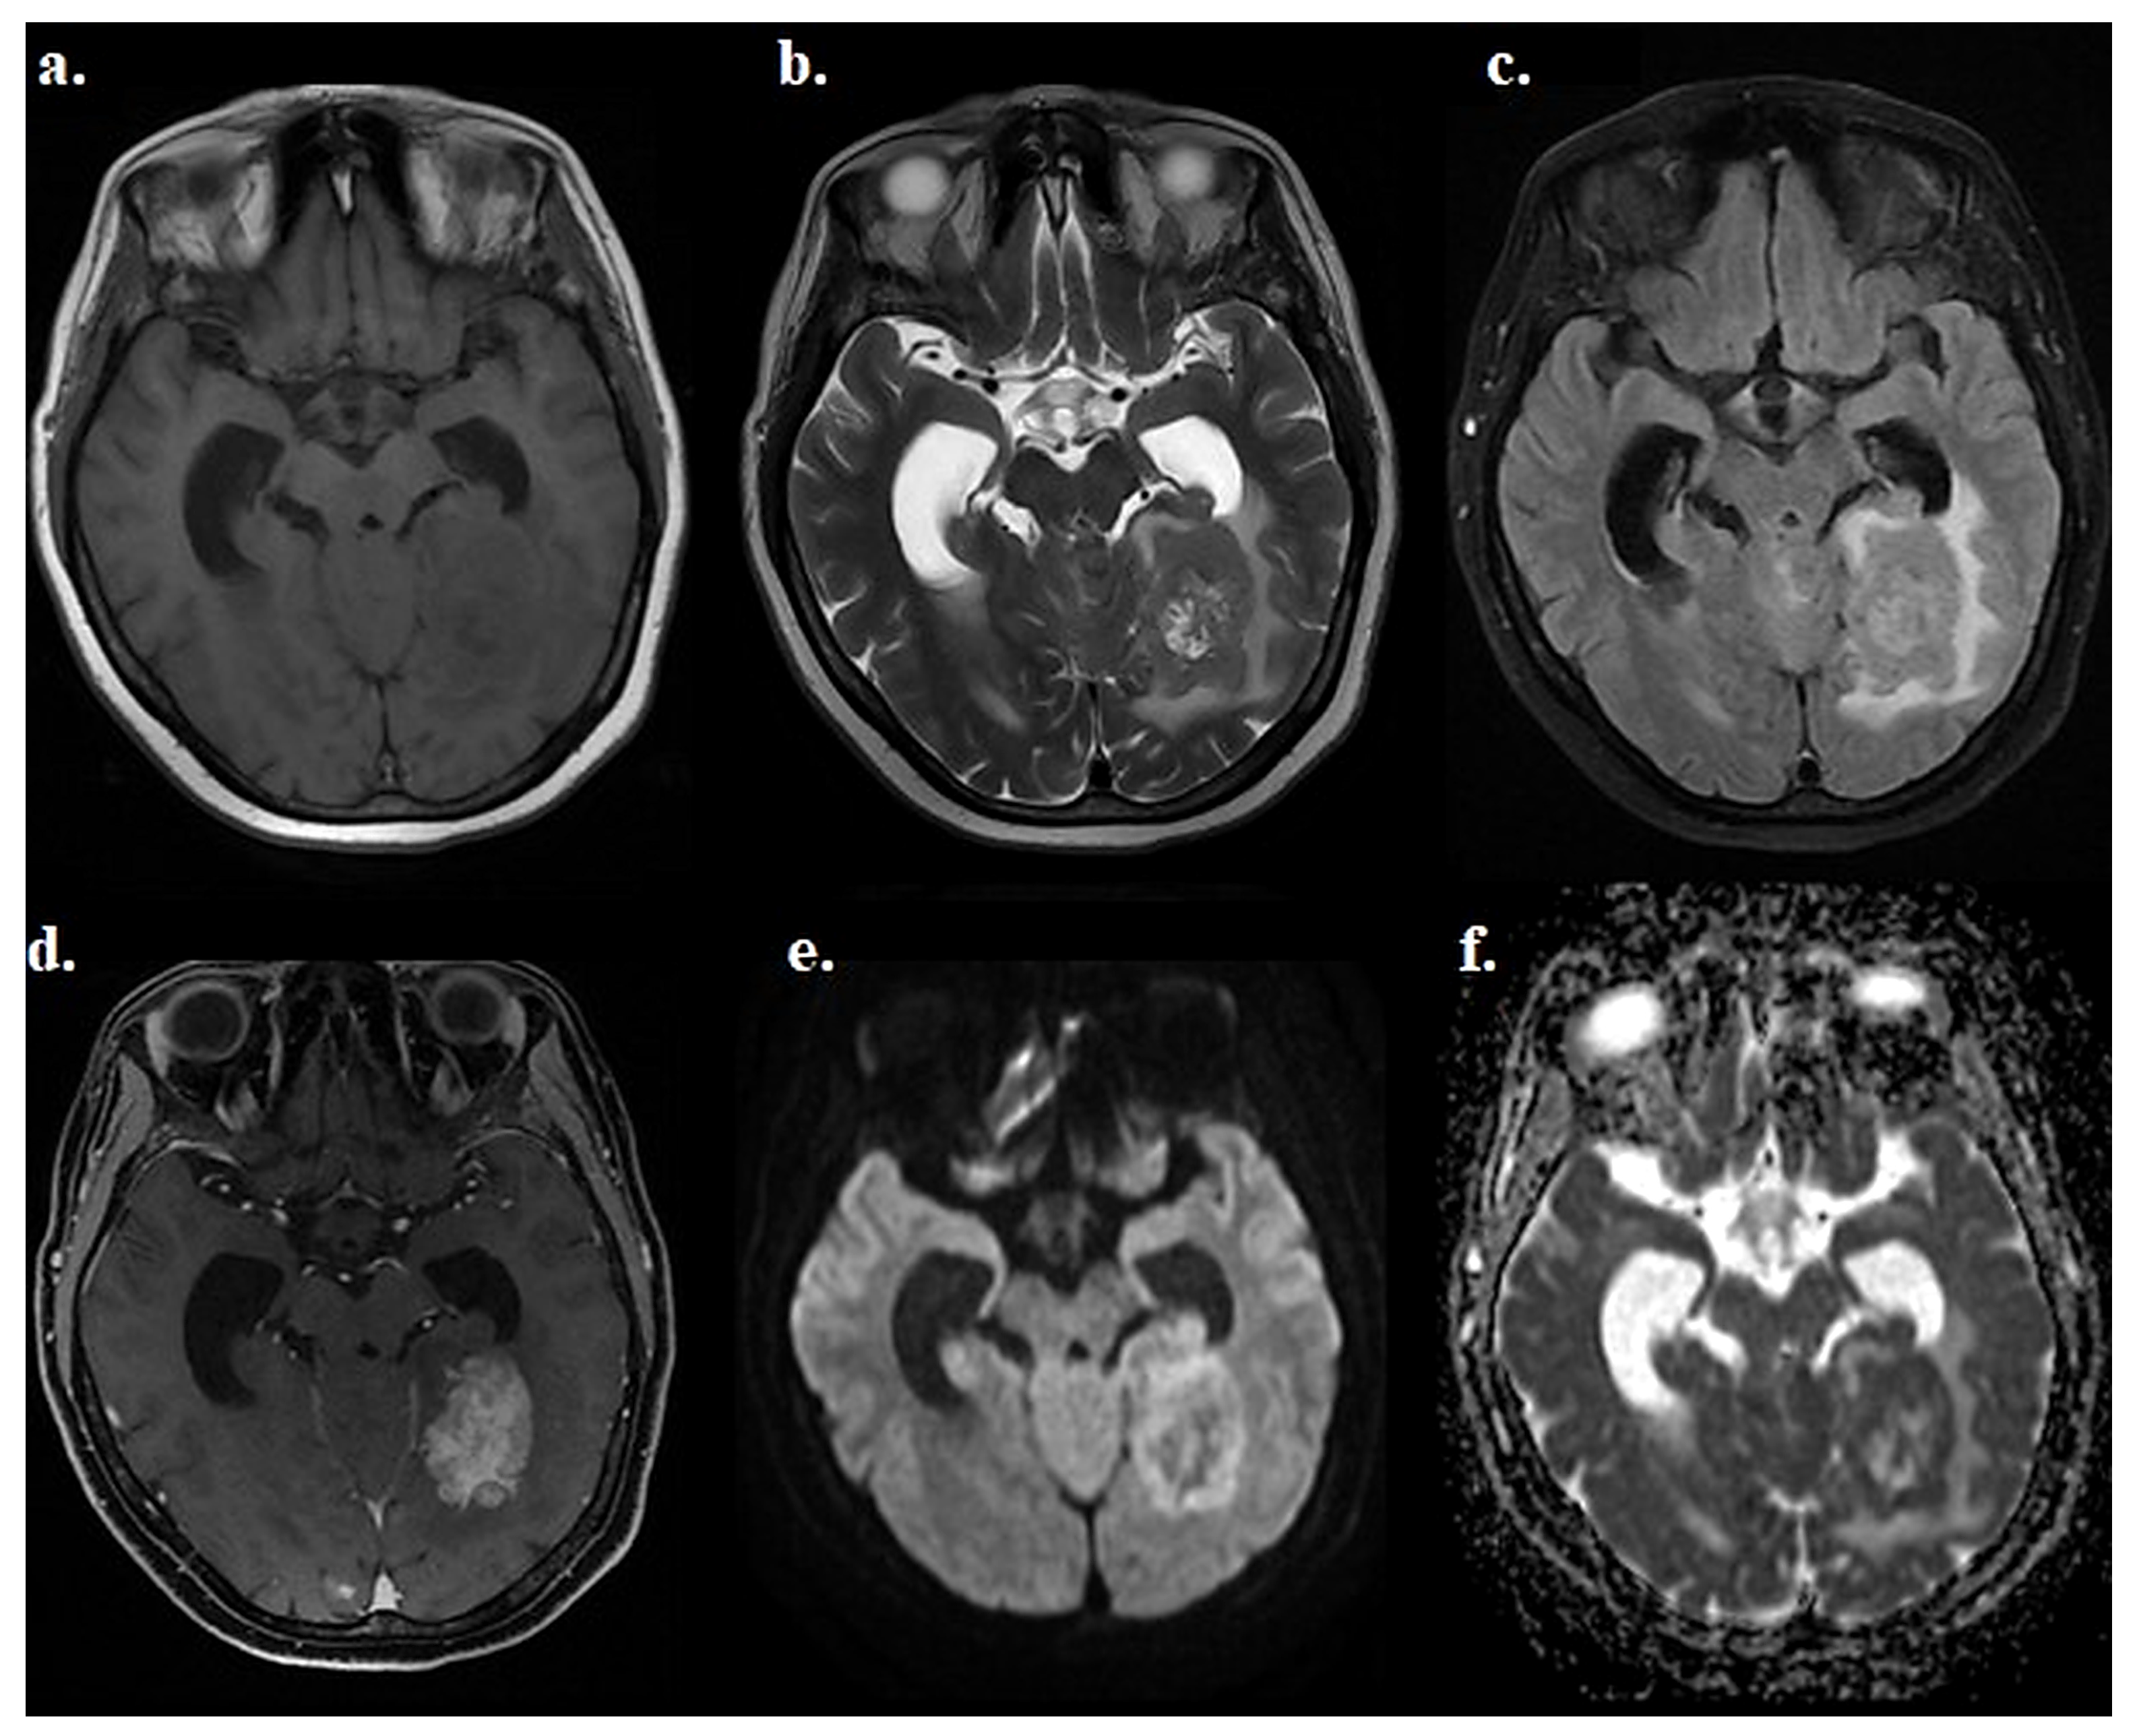

2.4. Lesion Identification and Selection

2.5. Post-Processing and ADC Histogram Analysis